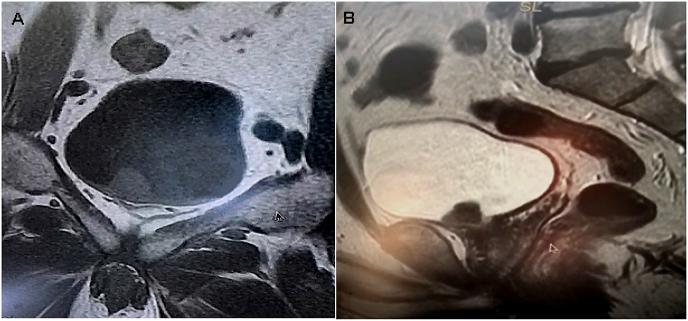

Urol Case Rep. 2018 Mar 1;18:29-30. doi: 10.1016/j.eucr.2018.02.020. eCollection 2018 May.